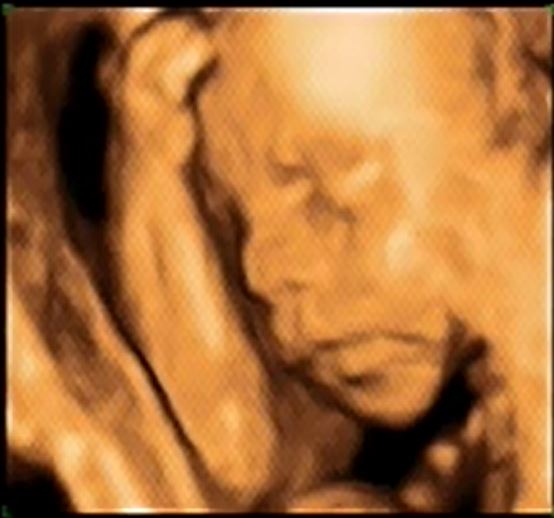

Na naszym piątkowym usg mój szkrab chętnie pokazywał tylko jedną część ciała:

Z resztą było dużo gorzej bo strasznie się wiercił tak, że nawet pani dr która robiła badanie stwierdziła, że wyjątkowo ruchliwy jest i nawet chwili nie usiedzi w jednym miejscu. I dostał ksywkę "sprinter"

Ale męczyliśmy go dość długo (badanie trwało 50min) i sprawdzone zostały wszystkie niezbędne parametry. Z czego wynika, że waga obywatela to już ponad 500 gram.